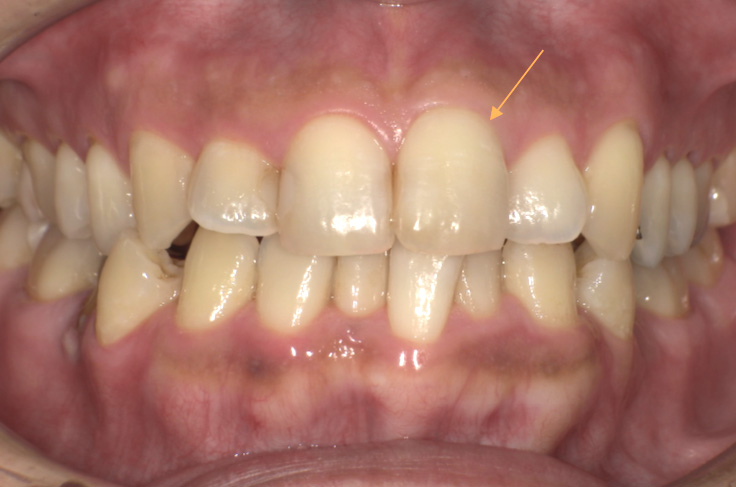

治療前の写真

治療後の写真

| 主訴 | 左上の1番の歯の色味が気になる |

|---|---|

| 治療期間 | 約1か月 |

| 治療費 | 1回¥5,500×3回 (約1~2週間で薬剤交換) |

| 治療内容 | ウォーキングブリーチという治療です。 神経がない歯の内部に薬剤を入れ内側から白くしていく方法です。 色味を確認しながら薬剤を交換し色味が納得できたタイミングで穴を封鎖します。 |

| 治療のリスク | 白さが後戻りすることがあります。色味の変化に個人差があります。 歯質が脆い場合や残っている歯の量が少ない場合には、ウォーキングブリーチは適応となりません。その場合は、歯を保護し形態を修復することができるクラウンが適応となります。 妊娠中や未成年の方、無カタラーゼ症の方・根の病変がある場合は、ウォーキングブリーチは行うことができません。 |